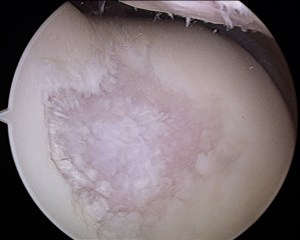

knee with a hammer. So naturally I finished the pull (475), then dropped it and walked around trying to determine what had just happened. Turns out I suffered a bone bruise…whether this happened before the deadlift or during is open to debate. Regardless the MRI showed a 1 inch bone bruise: RX: stay off of it. I did the best I could, but I was busy traveling and teaching MovNat at that time…so realistically I did myself no favors-that was last week of december. **take home point for you: don’t do MRIs the last week of december because you’ll lose that $500 towards your insurance deductible!**  Fast forward to April, the knee is feeling good, no pain or anything while jumping, climbing stairs, squatting, or for the first time since the injury pulling off the floor.  So I went slow and did some fun lifting for 2 weeks-when all of a sudden after 2 workshops I taught in NYC the knee felt worse than it had in a long time. So I went back to doing very very little, and things worked out so that I ended up leaving movnat, returning home to San Diego to start my own business coaching fitness and movement in San Diego.  I also followed up with another MRI on the knee which showed a ‘HOLE’ in my medial femoral condyle. This was not exciting. The original doctor said I should wait 4 months and do another MRI to see what happens, whether it gets better or worse.  I thought about it, and decided to find another doctor who deals primarily with athletes and not geriatrics/degenerate regular population that doesn’t take movement, health and vitality

tibial plateau after being cleaned up…aka removing rough flaking articular cartilage

seriously. The second doctor strongly suggested we scope the knee; I agreed this was a good idea so that we could actually see WTF was going on (my surgery actually got moved up because floating cartilage got wedged and I couldn’t straighten or put weight on the leg). In surgery it turned out that the spot on the knee had a pretty good amount of damage to the articular cartilage, but wasn’t actually a hole, I still had half the thickness of my articular cartilage. This was good.  So they cleaned up the medial condyle, the tibial plateau, behind the knee cap (all had rough, fraying articular cartilage), and removed a couple floating pieces of cartilage.